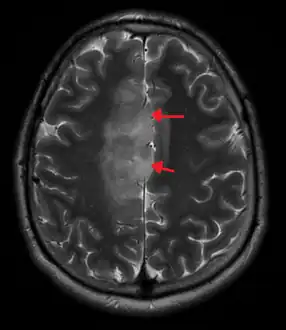

An X-ray computed tomography (CT) or magnetic resonance imaging (MRI) scan is necessary to characterize the anatomy of this tumor as to size, location, and its heter/homogeneity. However, final diagnosis of this tumor, like most tumors, relies on histopathologic examination (biopsy examination).[3]

A oligoastrocytoma on MRI